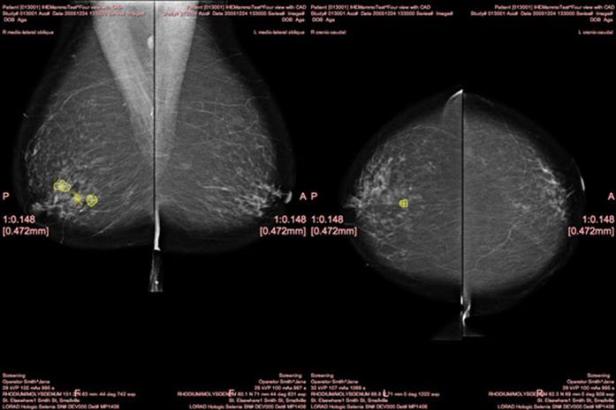

La inclusión de programas y aplicaciones informáticas para generar CAD Computer aided detection (Detección asistida por ordenador) en el informe radiológico empezó con relativas certezas en el diagnóstico de la imagen de mama mamográfico en los inicios de la década de 2000.

Contando con noticias con un titular tan llamativo como extraño que apareció a finales de agosto pasado ‘Los radiólogos detectan cáncer de mama en un ‘abrir y cerrar de ojos’ (Radiologists detect breast cancer in ‘blink of an eye’, sciencedaily, 29 Agosto 2016), y que se refiere a cierta capacidad intuitiva y bajo experiencia en el diagnóstico que un Radiológo puede tener a pesar de no visualizar hallazgos totalmente claros, los CAD en mamografía fueron el arranque para investigar qué posibilidades tendría un programa informático para aumentar el nivel de certidumbre diagnóstica, y que por tanto mejore las prestaciones de un servicio de diagnóstico por imagen en los éxitos o resultados medibles en los informes de los radiólogos.

Los CAD son programas que almacenan una cantidad tremenda de datos previos sobre una serie de pruebas diagnósticas por imagen. Por ejemplo: un CAD de mamografía almacena un gran volumen de datos de hallazgos diagnosticados en mamografías, y que a través de la codificación en los píxeles, permite identificar o asociar como lo hacen los detectores de huellas dactilares. Además, los CAD incorporan herramientas en el flujo de trabajo del radiólogo, y cuando te detecta una lesión o hallazgo te ofrece sistemas de ayuda de información y decisión sobre la clasificación del hallazgo, y otras comparativas posibles.